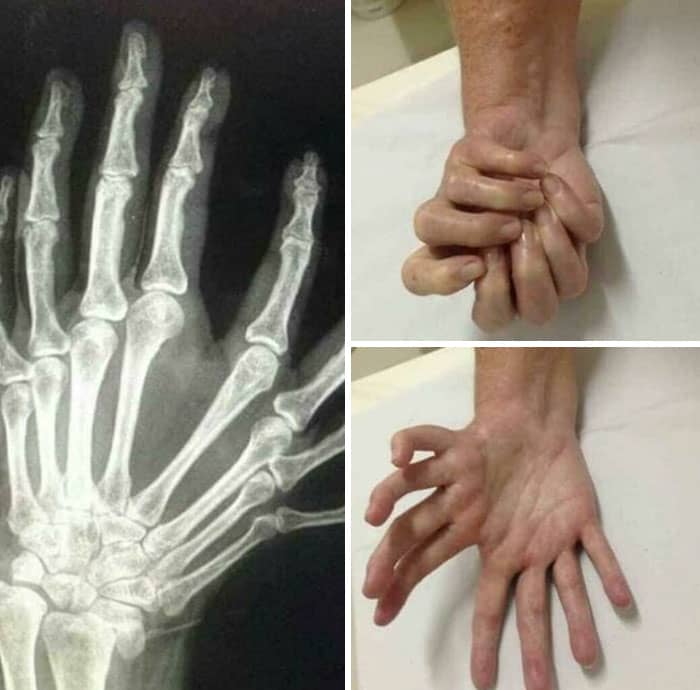

#54 Dupuytren’s Contracture Symptoms

Dupuytren contracture is a painless condition that causes one or more fingers to bend toward the palm of the hand. The affected fingers can’t straighten completely. Knots of tissue form under the skin. They eventually create a thick cord that can pull the fingers into a bent position.